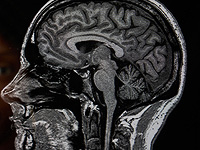

В конце прошлого года в Великобритании умер молодой мужчина, которого называли самым юным пациентом с деменцией в стране – ему было всего 24 года. Житель Норфолка Андре Ярхам узнал о своем диагнозе в 22-летнем возрасте. Ярхам завещал свой мозг ученым для научных исследований, сообщает BBC.

Первые тревожные изменения в поведении сына Фэрбэрн заметила вскоре после своей свадьбы с отчимом Андре, Аластером, в ноябре 2022 года. Молодой человек стал более рассеянным и иногда вел себя неадекватно. Обследование в университетской больнице Норфолка и Норвича выявило необычное уменьшение объема мозга, а окончательный диагноз был поставлен в больнице Адденбрука в Кембридже.